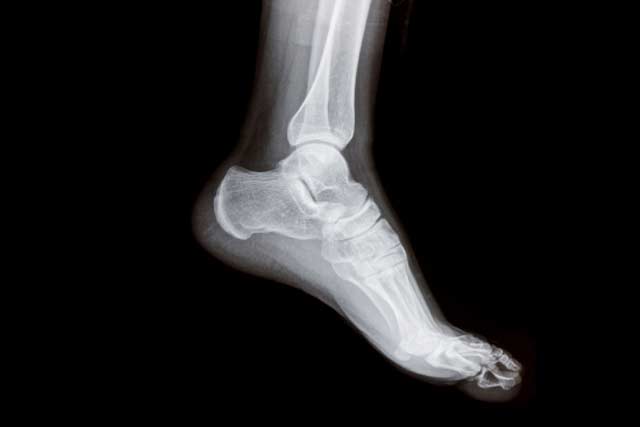

At the Nuffield Orthopaedic Centre we have a foot and ankle service dedicated to the diagnosis, investigation and treatment of all types of foot and ankle problems deriving from sports injuries, accidents, hereditary and developmental conditions and all aspects of arthritis.

We perform thousands of procedures annually. We are a tertiary referral centre and people are referred to us with complex musculoskeletal conditions both countrywide and internationally.

We are also a world-leading centre in minimally-invasive-surgery, ankle replacements and management of complex foot problems. In addition, we also offer, and undertake, more standard procedures and services.